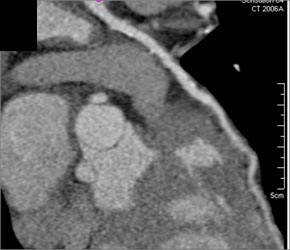

Left Main Coronary Artery Aneurysm